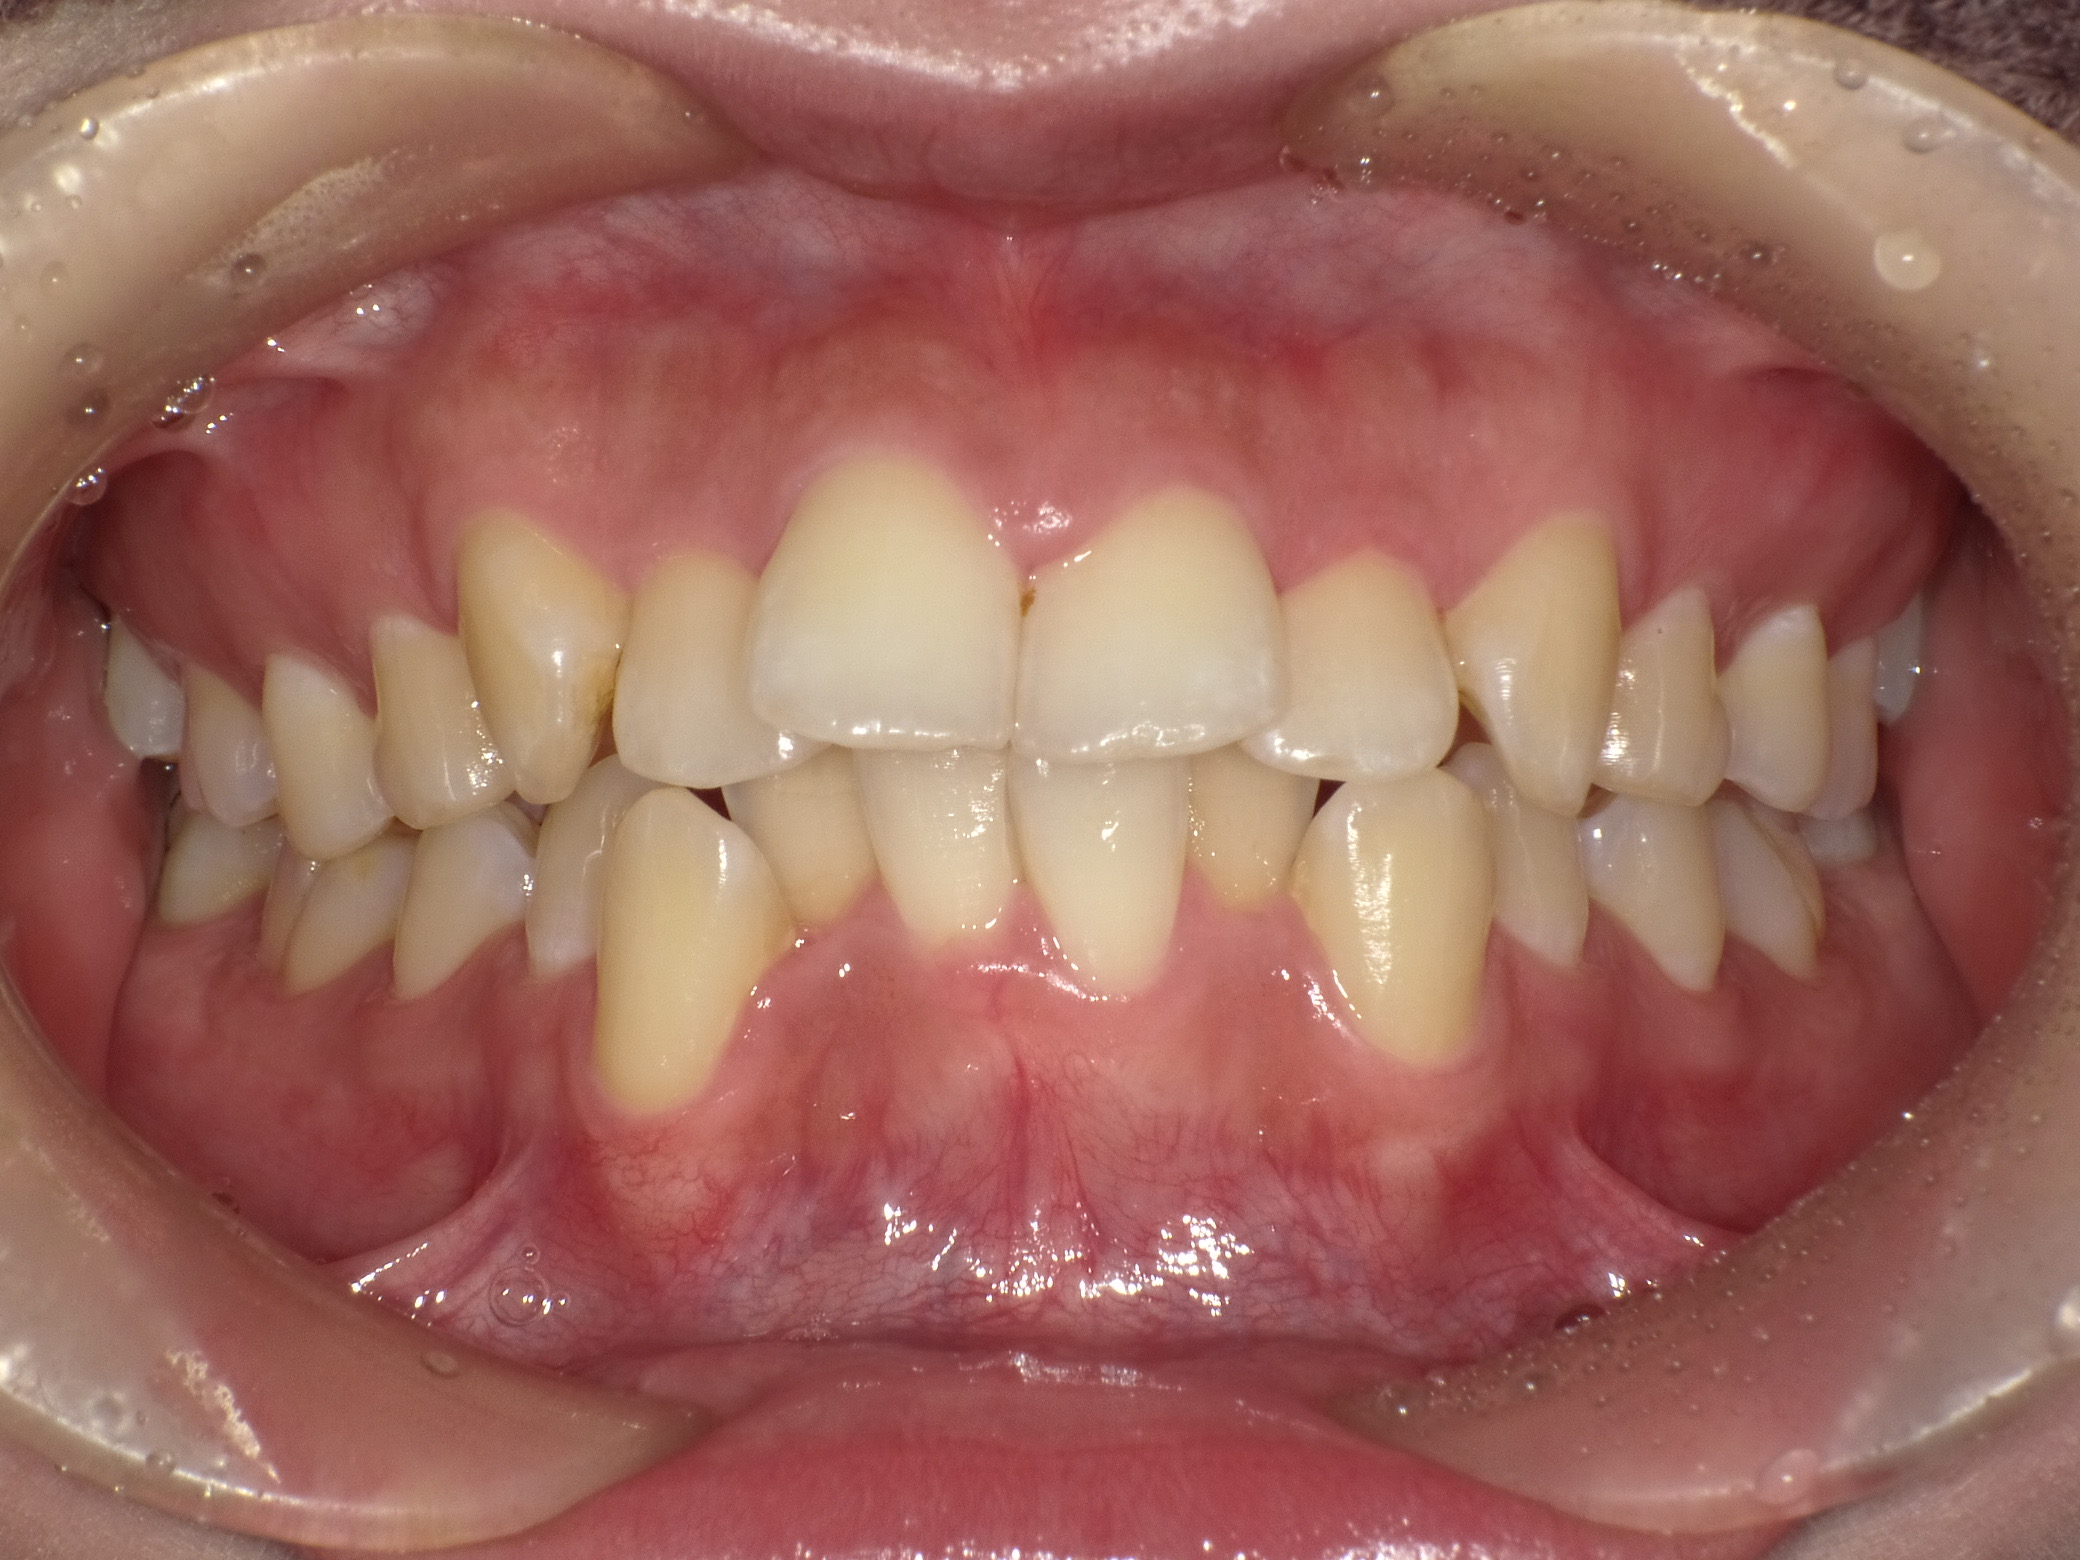

症例②

症例2_治療前 症例2_治療後

年齢・性別 31才・男性

治療方法 ブラケット矯正

治療期間 3年

治療総額 850,000円

特記事項 抜歯あり(4本抜歯)